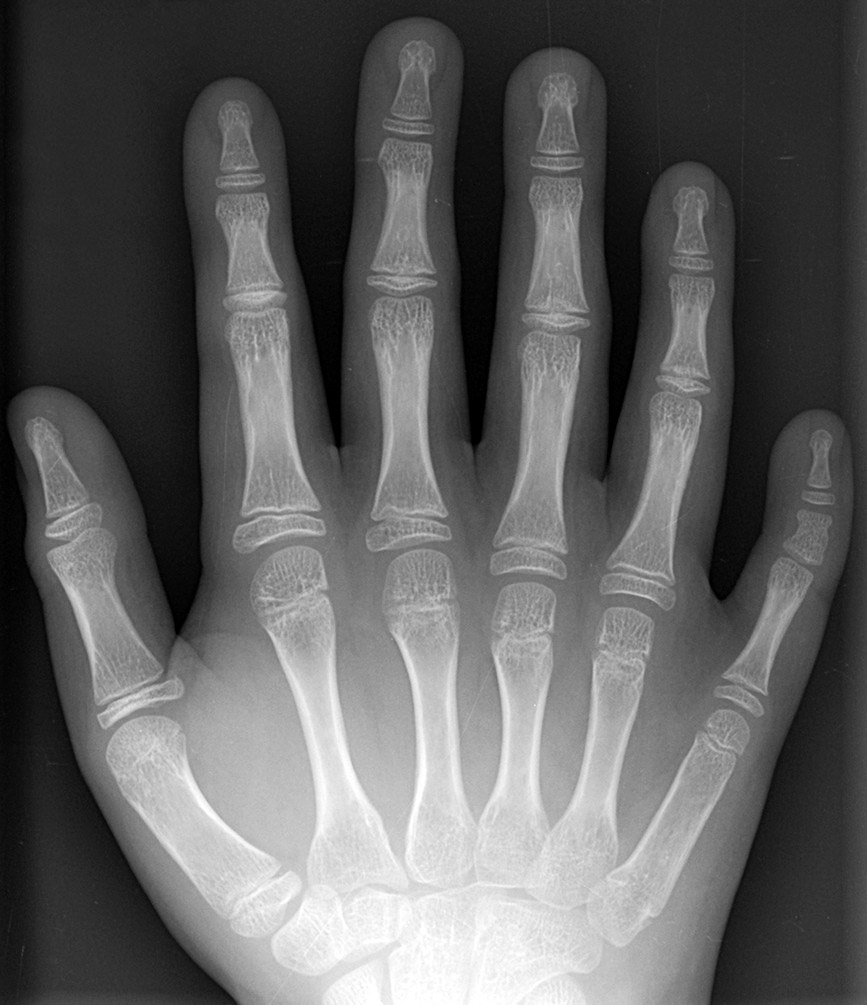

La polidactilia es un trastorno genético congénito que consiste en nacer con más de cinco dedos en manos o pies, comúnmente seis en total, detectado al nacimiento o por ecografía prenatal.​ Afecta aproximadamente a uno de cada 500-1000 bebés, con mayor incidencia en hombres y ciertos grupos étnicos, y suele ser un dedo extra supernumerario que puede ser funcional o bien haber tenido un desarrollo menor que lo haga inútil.

Radiografía de una mano derecha con duplicación de uno de sus dedos. Original work by author, CC BY-SA 3.0, https://commons.wikimedia.org/w/index.php?curid=120503